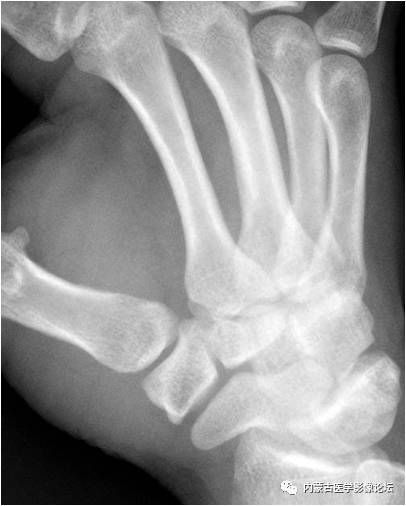

拇指籽骨:拇指指间关节籽骨(箭)较小且略呈三角形,与拇指掌指关节籽骨(箭头)不同,勿误认为撕脱骨折。

拇指掌腕关节“台阶征”:手正位片上(相当于拇指掌腕关节斜位),拇指掌腕关节的外形有一定程度的失真,关节边缘(箭)形成“台阶”样改变,与“半脱位”征象类似。手斜位片(相当于拇指掌腕关节正位)可以证实正位所见为假象。